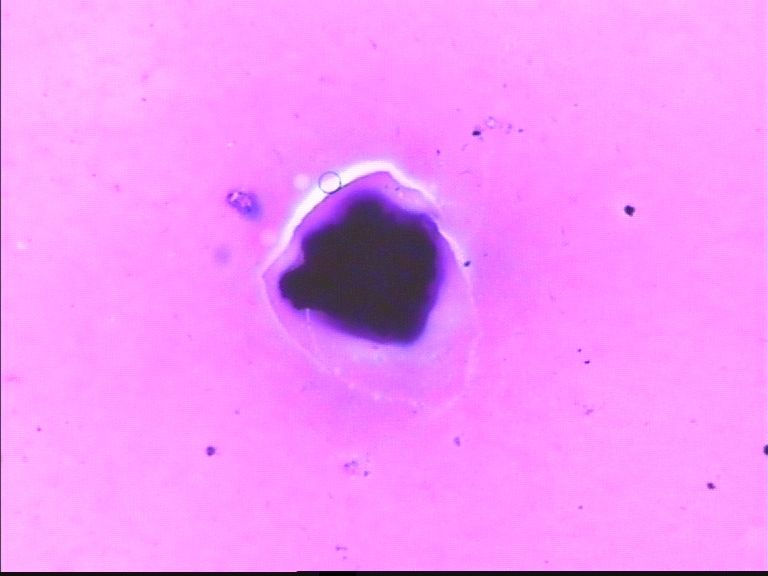

67岁胸水,有风湿病

深染的不是细胞(就是细胞,看不到结构,也不能诊断)。

看不清,不能诊断

制片质量欠佳,直接就看不出是什么了!

这些深染的是什么东西呢?好奇怪

深染的东西像杂质

深的可能是染料渣子

如果怀疑深染的东西里有细胞,那就加热加盖片的位置,取去盖玻片,在二甲苯里溶去封固胶,从高浓度到低浓度的酒精去掉二甲苯,直至水洗,再进入盐酸酒精里,再分化一会儿,看颜色退去些后,能不能看见有细胞结构。目前确实什么都看不见,也说不了什么。

没看出有设么异常细胞   图20好像有霉菌菌丝